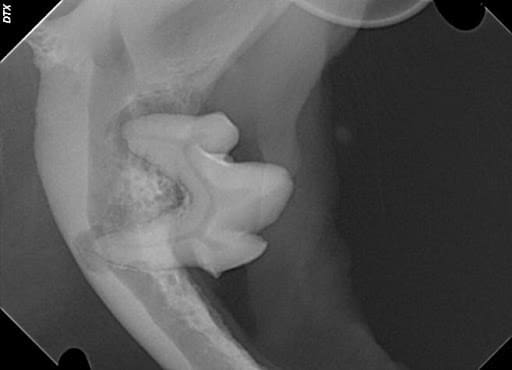

Figure 4 – A mandibular molar with severe periodontal disease that has progressed all the way to the tip of each root. Note the absence of all other local teeth that have already been lost to periodontal infection.

Can periodontal disease cause a tooth to be abscessed? Sometimes it can. Periodontal disease starts at the margin of the gumline when plaque bacteria infect the gingival tissues and progress down the root of the tooth. Plaque bacteria cause an intense reaction of the immune system that results in the breakdown of the bone and soft tissues around a tooth. If the infection progresses all the way down to the tip of a root, a true abscess may occur and result in the pulp becoming infected through the apex rather than the crown of a tooth. This is often referred to as a “perio-endo” infected tooth.

Teeth that have periodontal infection can often be treated and saved if the infection has not excessively destroyed surrounding tissues and infected the pulp. However, periodontally infected teeth that have become “perio-endo” teeth most often should be surgically extracted.